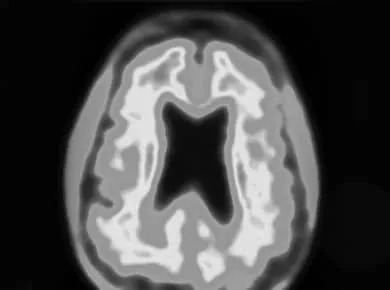

The cause of dementia in dogs is that “A consistent finding in both is neuron loss and cortical atrophy as well as deposition of predominantly diffuse beta-amyloid plaques. Most deposition in dogs is in the cerebral cortex and the hippocampus, an area associated with memory. In senile dogs a correlation exists between the quantity of beta-amyloid accumulation and the degree of cognitive decline. ” REF 1